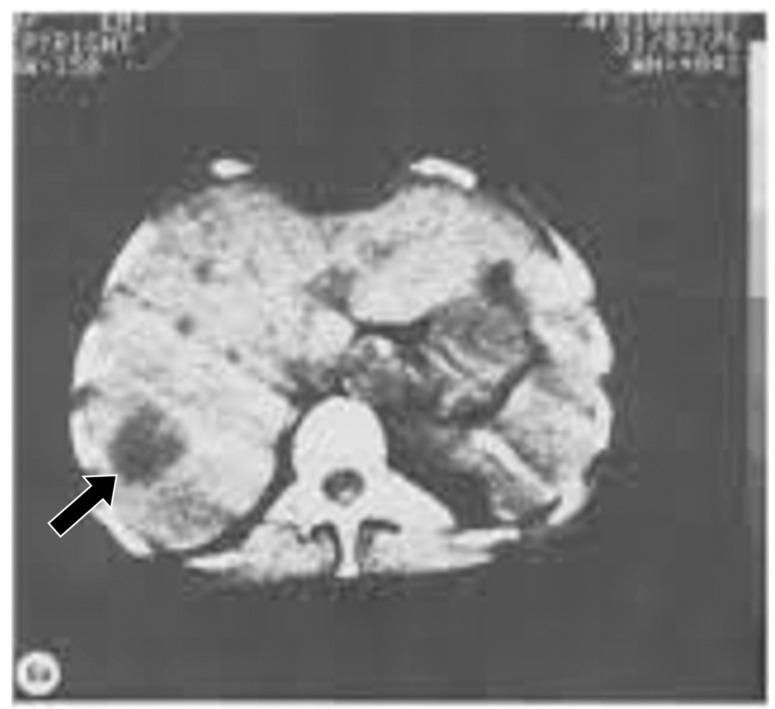

Ultra-high contrast (UHC) MRI describes forms of MRI in which little or no contrast is seen on conventional MRI images but very high contrast is seen with UHC techniques. One of these techniques uses the divided subtracted inversion recovery (dSIR) sequence, which, in modelling studies, can produce ten times the contrast of conventional inversion recovery (IR) sequences. When used in cases of mild traumatic brain injury (mTBI), the dSIR sequence frequently shows extensive abnormalities in white matter that appears normal when imaged with conventional T-fluid-attenuated IR (T-FLAIR) sequences. The changes are bilateral and symmetrical in white matter of the cerebral and cerebellar hemispheres. They partially spare the anterior and posterior central corpus callosum and peripheral white matter of the cerebral hemispheres and are described as the whiteout sign. In addition to mTBI, the whiteout sign has also been seen in methamphetamine use disorder and Grinker's myelinopathy (delayed post-hypoxic leukoencephalopathy) in the absence of abnormalities on T-FLAIR images, and is a central component of post-insult leukoencephalopathy syndromes. This paper describes the concept of ultra-high contrast MRI, the whiteout sign, the theory underlying the use of dSIR sequences and post-insult leukoencephalopathy syndromes.

超高对比(UHC)MRI 描述了这样一些 MRI 形式,在常规 MRI 图像上几乎没有或没有对比,但在 UHC 技术中可以看到非常高的对比。其中一种技术使用分裂相减反转恢复(dSIR)序列,在建模研究中,该序列可以产生比常规反转恢复(IR)序列高十倍的对比度。当用于轻度创伤性脑损伤(mTBI)时,dSIR 序列经常在白质中显示出广泛的异常,而在使用常规 T 液衰减反转恢复(T-FLAIR)序列成像时,白质看起来正常。这些变化在大脑和小脑半球的白质中是双侧对称的。它们部分保留了前中央和后中央胼胝体以及大脑半球的外周白质,被描述为“白化征”。除了 mTBI 之外,在没有 T-FLAIR 图像异常的情况下,该白化征也出现在苯丙胺使用障碍和 Grinker 髓鞘病(缺氧后迟发性白质脑病)中,是创伤后白质脑病综合征的一个核心组成部分。本文描述了超高对比 MRI、白化征、dSIR 序列使用的理论以及创伤后白质脑病综合征的概念。